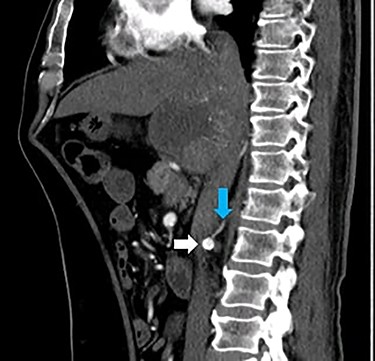

A 66-year-old male was referred to our institution for management of a liver lesion found incidentally on abdominal imaging. There was no significant past medical or surgical history, and he was asymptomatic. On physical examination, the patient was vitally stable and all systemic examinations were unremarkable. Contrast-enhanced triple phase abdominal computed tomography (CT) scan showed an arterial enhancing lesion in Segment I of liver with early washout, consistent with HCC (Fig. 1). This lesion received blood supply from the right renal artery (Fig. 2). Ultrasound-guided biopsy was performed to confirm the diagnosis of HCC, and subsequently the patient successfully underwent TACE. Figures 3 and 4 show the angiographic findings of the right renal artery branch supplying the lesion. Repeat CT scan at 6-week follow-up showed no evidence of residual disease.

CT scan sagittal section arterial phase showing a branch (blue arrow) originating from the right renal artery (white arrow) supplying the lesion in Segment I of the liver.